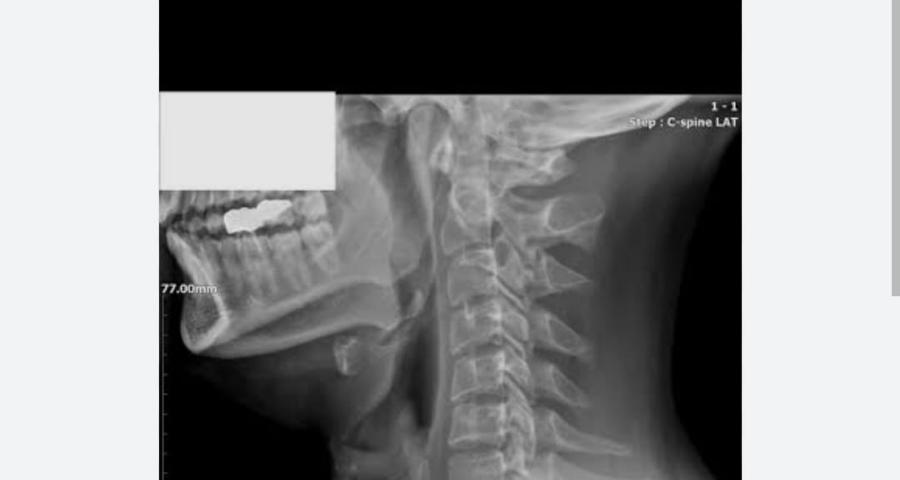

Boyun Düzleşmesi Nedir?  Tedavisi ve Belirtileri Nelerdir?